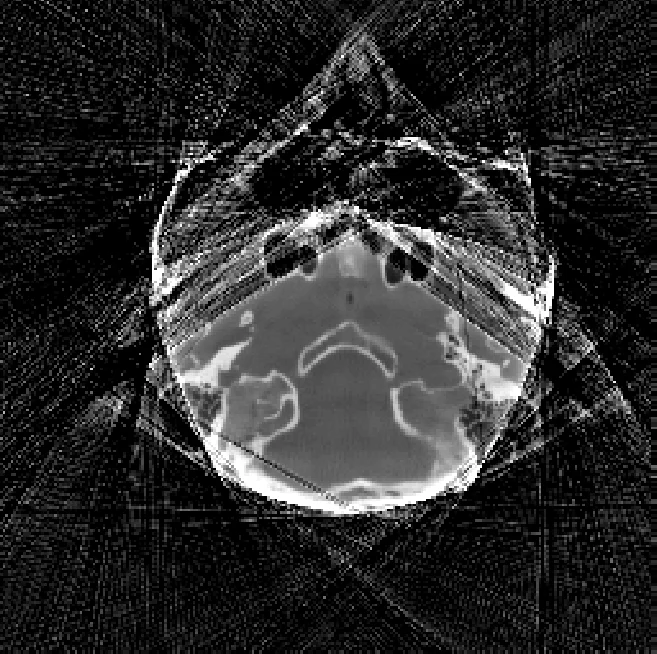

실험에서는 1차원 희소 신호 복원과 CT 재구성 두 영역에서 성능을 검증한다. 1차원 실험에서는 포화 비율이 높아도 M1bit‑CS가 비포화 데이터와 거의 동등한 복원 정확도를 보였으며, λ와 τ 파라미터 선택이 결과에 큰 영향을 미치지 않음을 확인했다. CT 재구성 실험에서는 knee phantom과 시뮬레이션 임상 데이터를 사용했으며, 기존의 외삽 기반 방법이 남기는 스트리킹 및 캡핑 아티팩트가 현저히 감소하였다. 정량적으로는 평균 절대 오차(MAE)와 구조적 유사도(SSIM) 지표가 모두 개선되었으며, 특히 고밀도 영역에서 HU 값 복원이 크게 향상되었다.